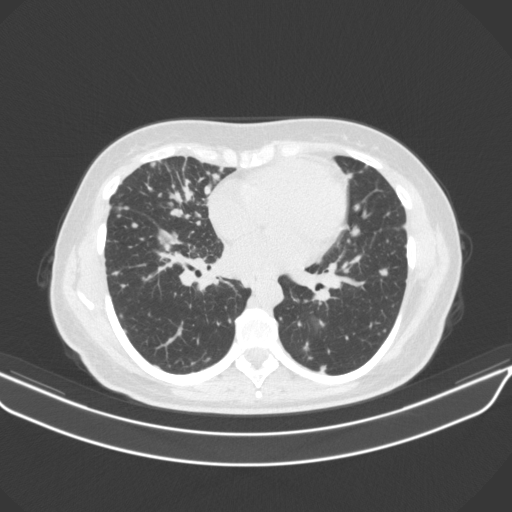

Targeted Slice 70 - Lung Window Analysis (Generated vs Real Venous)

0.728

Lung SSIM

109.0

Lung RMSE

48.5

Lung MAE

Average Lung Window Metrics Across All Slices (133 slices) - Generated vs Real Venous

0.727

Lung SSIM (Avg)

108.6

Lung RMSE (Avg)

46.1

Lung MAE (Avg)

Generated VENOUS CT scan (A→B translation)

No window - Raw intensity values

Lung window (WL -600, WW 1500 β†’ Low βˆ’1350, High +150)